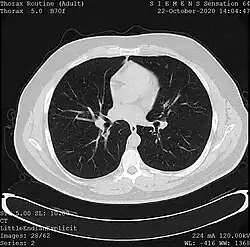

Tomography

Tomography is the imaging by sections or sectioning. The main such methods in medical imaging are:

- X-ray computed tomography (CT), or Computed Axial Tomography (CAT) scan, is a helical tomography technique (latest generation), which traditionally produces a 2D image of the structures in a thin section of the body. In CT, a beam of X-rays spins around an object being examined and is picked up by sensitive radiation detectors after having penetrated the object from multiple angles. A computer then analyses the information received from the scanner's detectors and constructs a detailed image of the object and its contents using the mathematical principles laid out in the Radon transform. It has a greater ionizing radiation dose burden than projection radiography; repeated scans must be limited to avoid health effects. CT is based on the same principles as X-ray projections but in this case, the patient is enclosed in a surrounding ring of detectors assigned with 500–1000 scintillation detectors[19] (fourth-generation X-ray CT scanner geometry). Previously in older generation scanners, the X-ray beam was paired by a translating source and detector. Computed tomography has almost completely replaced focal plane tomography in X-ray tomography imaging.